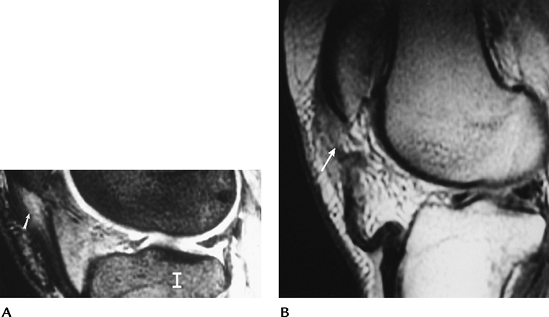

Meniscal Lesions: Postoperative Meniscus

-

Image features applied to diagnosis of

Intra-articular gadolinium may improve

gadolinium is 92% accurate for detection of retear. -

Arthroscopy is most useful in complex or equivocal cases.

![]() |

FIGURE 5-26 (A) Sagittal MR image of a normal medial meniscus. (B) Partial meniscectomy and peripheral repair. There is increased signal in the region of the repair (arrow). The central meniscus appears normal. (C) Sagittal T2-weighted image after complete meniscectomy (arrow).